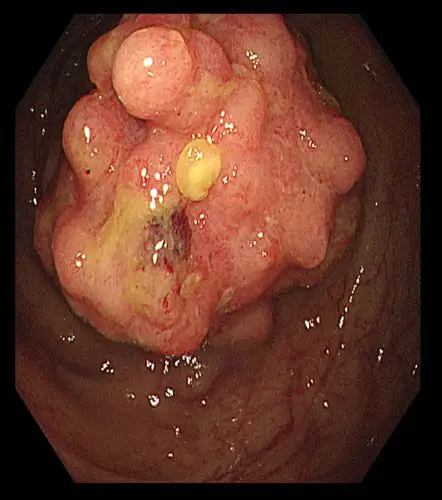

结肠巨大肿瘤,双镜联合根除